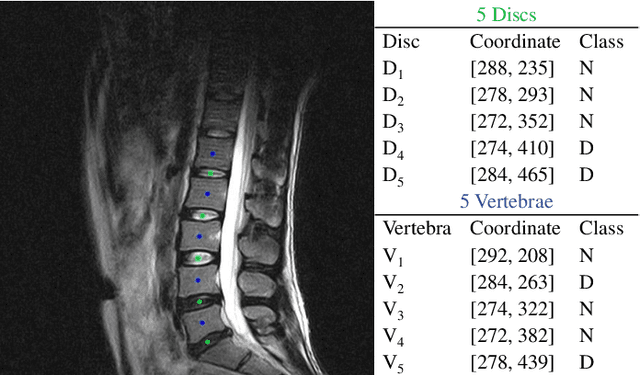

Abstract:Spinal degeneration plagues many elders, office workers, and even the younger generations. Effective pharmic or surgical interventions can help relieve degenerative spine conditions. However, the traditional diagnosis procedure is often too laborious. Clinical experts need to detect discs and vertebrae from spinal magnetic resonance imaging (MRI) or computed tomography (CT) images as a preliminary step to perform pathological diagnosis or preoperative evaluation. Machine learning systems have been developed to aid this procedure generally following a two-stage methodology: first perform anatomical localization, then pathological classification. Towards more efficient and accurate diagnosis, we propose a one-stage detection framework termed SpineOne to simultaneously localize and classify degenerative discs and vertebrae from MRI slices. SpineOne is built upon the following three key techniques: 1) a new design of the keypoint heatmap to facilitate simultaneous keypoint localization and classification; 2) the use of attention modules to better differentiate the representations between discs and vertebrae; and 3) a novel gradient-guided objective association mechanism to associate multiple learning objectives at the later training stage. Empirical results on the Spinal Disease Intelligent Diagnosis Tianchi Competition (SDID-TC) dataset of 550 exams demonstrate that our approach surpasses existing methods by a large margin.